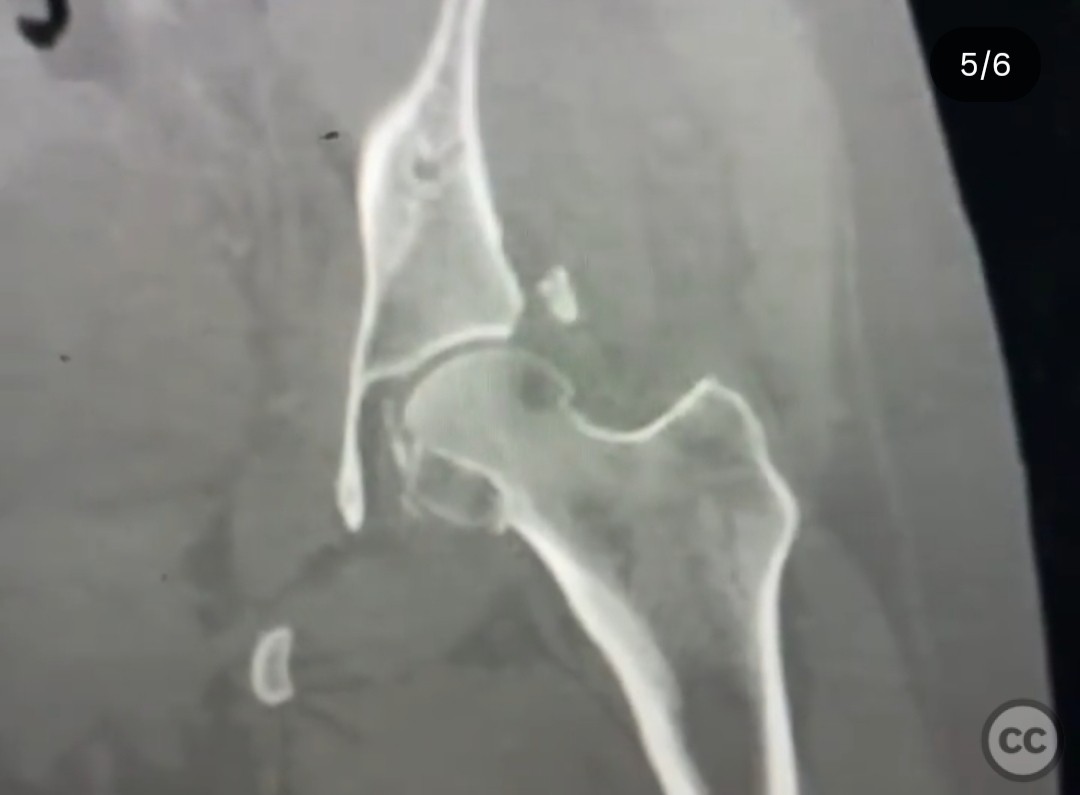

Clinical and radiological findings:  A 33-year-old female involved in a motor vehicle collision presented with a posterior hip dislocation accompanied by a comminuted supra-foveal femoral head fracture, a cranial peripheral posterior wall fracture, and a non-displaced femoral neck fracture. The injury is associated with a risk of sciatic nerve palsy and avascular necrosis (AVN).

Planning remarks:  The preoperative plan involved a Gibson approach with a trigastric slide osteotomy for anterior dislocation to address the femoral head fracture. The intention was to reconstruct the femoral head using a femoral head allograft due to a 20% pie slice defect. The posterior wall was to be addressed through capsulolabral repair with suture anchors and spring plates.